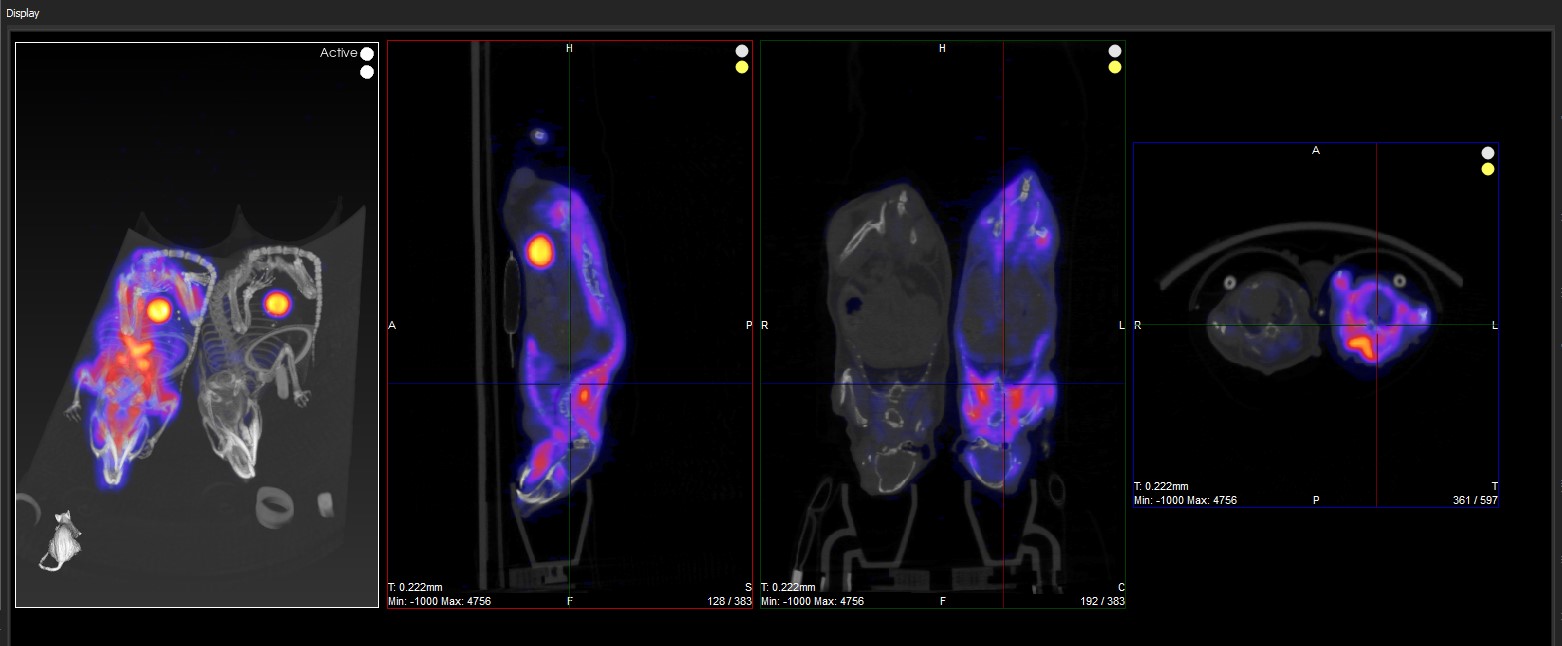

The Slice View (default) simultaneously displays images of single slices for the sagittal, coronal, and transversal views of the loaded data sets.

Slice View Display

In the example image below, the transversal view is the active view. The ← and → keys move the crosshairs towards the L (left side) and R (right side) in the transversal slice, respectively. Moving through the object to the left or right steps through the sagittal plane of the object; thus, the sagittal slice changes.

The ↑ and ↓ keys will move the crosshair towards P (posterior side) and A (anterior side). Both these sides are also visible in the sagittal slice of the object (rotated 90-degrees). Using the ↑,↓ keys in the transversal plane will shift the vertical crosshair in the sagittal plane, and step through the coronal views of the object.